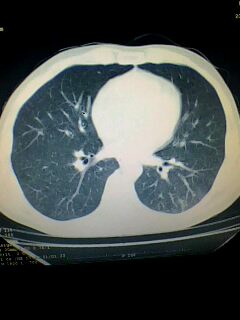

标题: CT28315:咳嗽咳痰咯血半月并胸痛 [打印本页]

标题: CT28315:咳嗽咳痰咯血半月并胸痛

图像资料欠清,建议强化,考虑周围型肺癌。

图像资料欠清,建议强化,考虑周围型肺癌。---支持

考虑左肺下叶周围型肺癌.